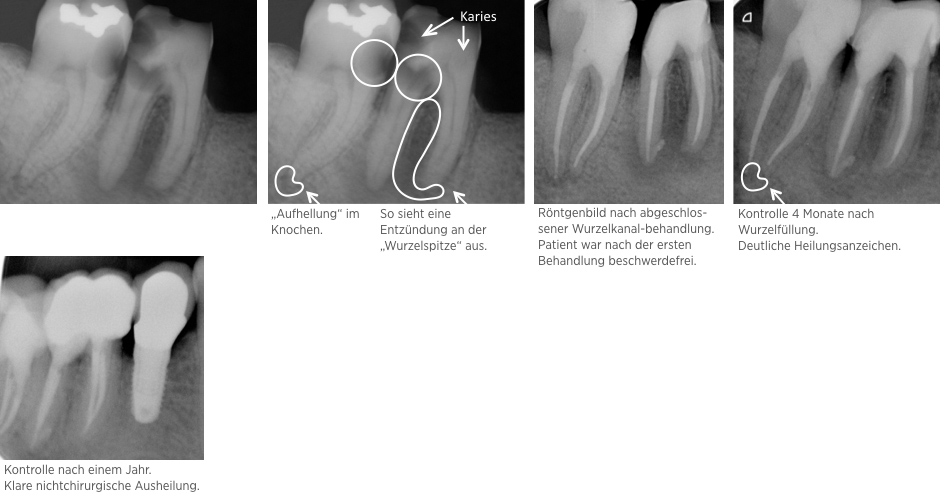

Fallbeispiele Endodontie

Hier sehen Sie einige erfolgreiche Endodontie Fallbeispiele

Fallbeispiel: Revision 46 (und 45) Recall 6 Monate

Bringt eine Wurzelkanalbehandlung nicht den gewünschten Erfolg, bedeutet dies nicht, dass ein Zahn nicht mehr zu erhalten ist. Mit einer Revisionsbehandlung können auch bereits wurzelkanalbehandelte Zähne langfristig erhalten werden!